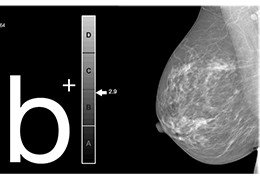

Eclipse 成像智能功能提供强大的处理能力和最佳质量的影像,同时减少质量错误并提高剂量效率。

凭借 AI、专有算法和先进的影像处理能力,提供出色的影像质量和无与伦比的诊断信心。

与标准影像处理相比,智能降噪功能可使客户降低辐射剂量,而不会损失影像质量。这在新生儿和儿科成像中尤其重要,在这种情况下以尽可能低的剂量成像至关重要。